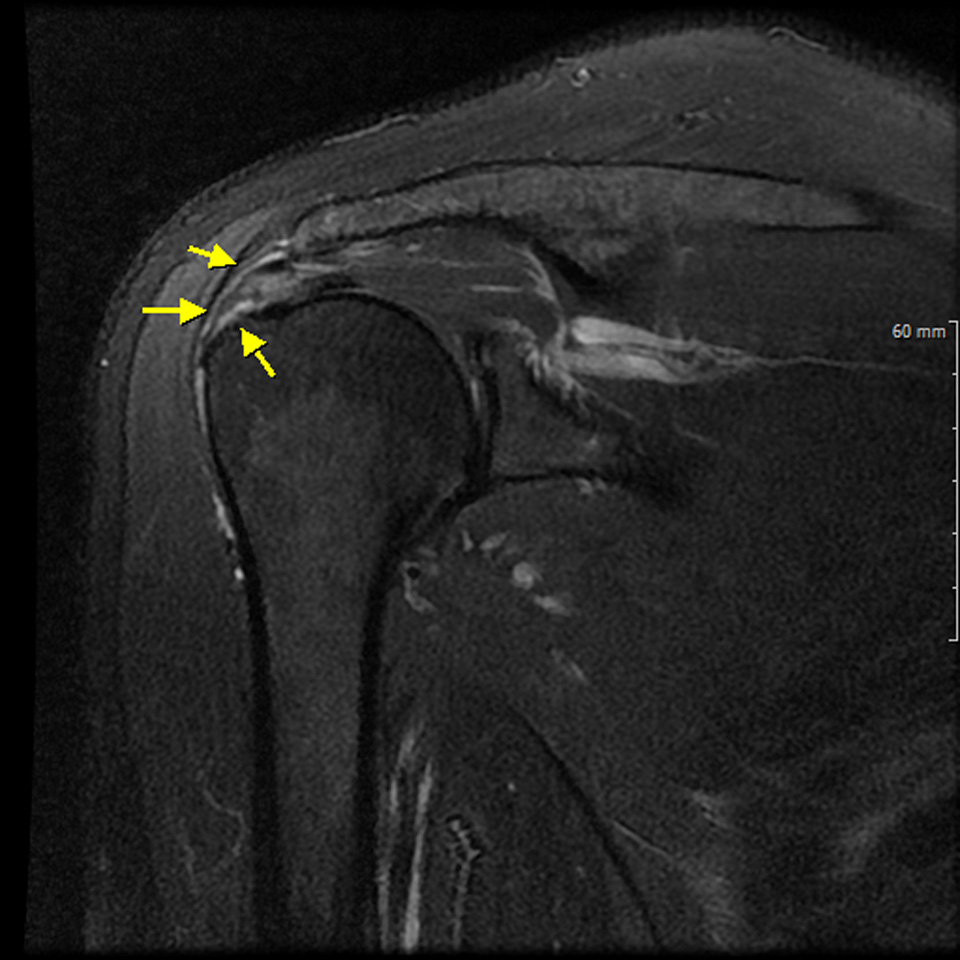

반드시 MRI 검사가 필요한데 가능하면 조영제를

넣고 찍는 MR-ARTHRO 검사를 시행해야

정확한 진단이 가능하다

수술전 MRI 에서 회전근개 파열을 확인할 수 있다.

- 환자 동의하에 게시된 이미지입니다.